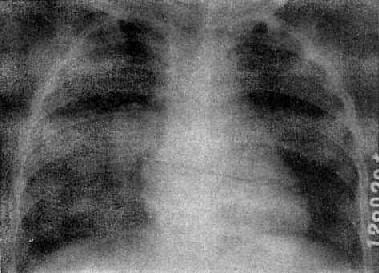

慢性血行播散型肺结核

图3-1-23 慢性血行播散型肺结核

两肺野布满大小不一、密度不同、分布不均的病灶,

下野较少,膈位置低而平